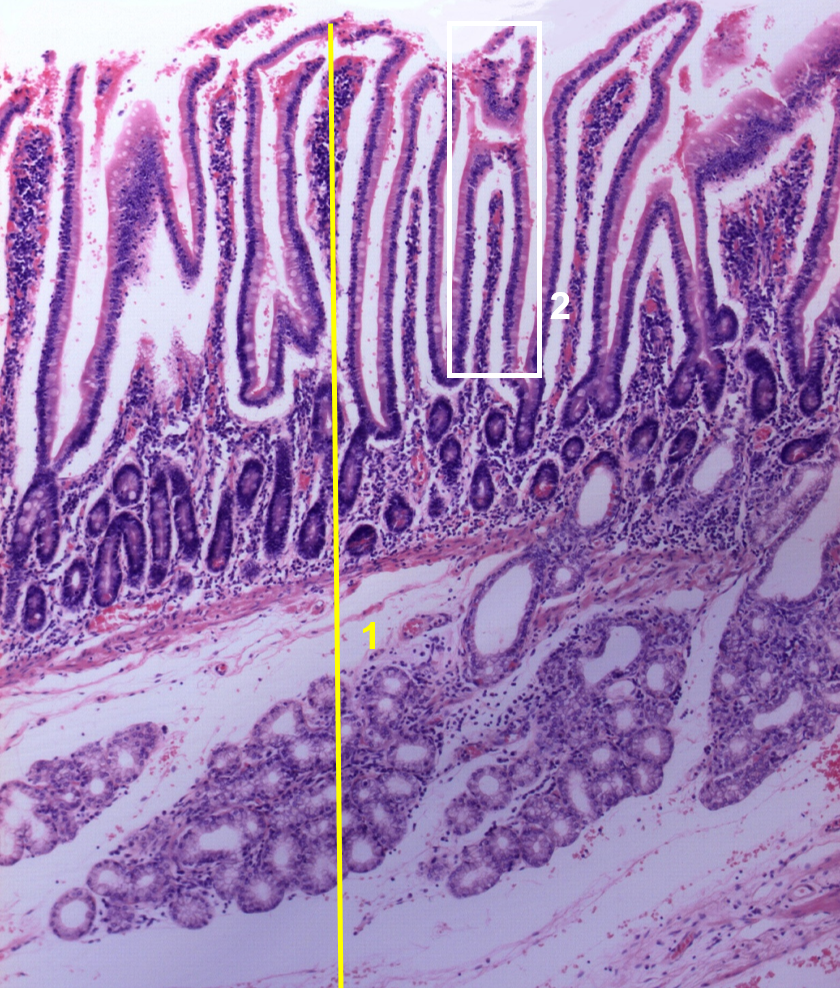

1: Íleon

2: Velocidades